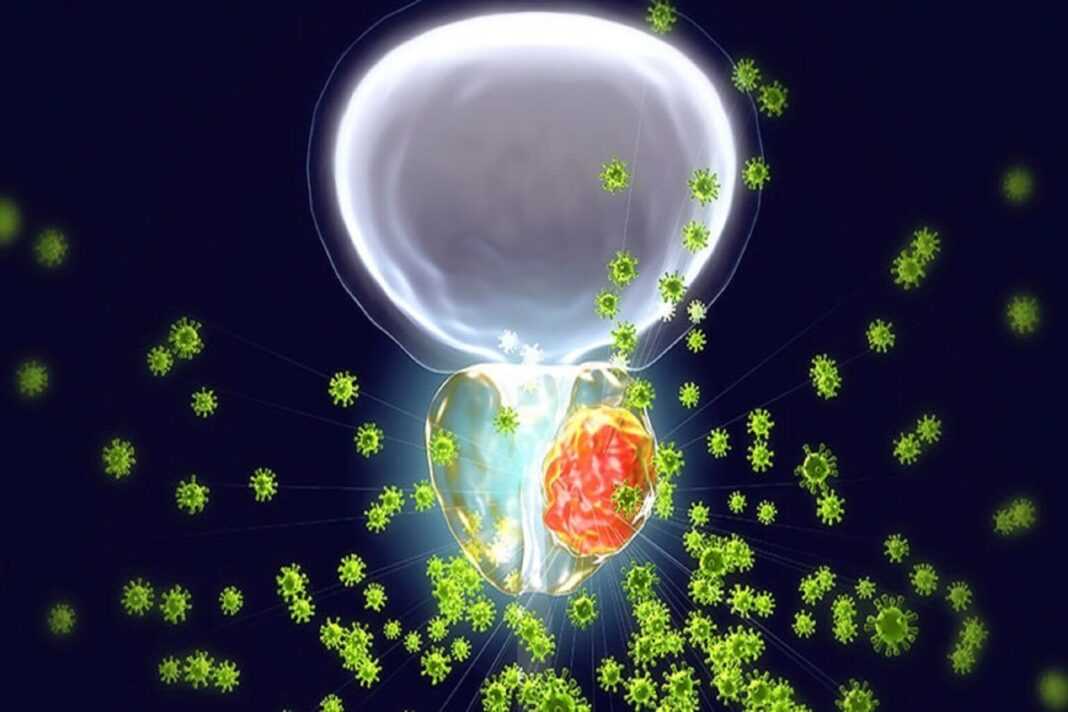

Oι ερευνητές εντόπισαν πέντε τύπους βακτηρίων που σχετίζονται με τον επιθετικό καρκίνο του προστάτη και λένε ότι τα ευρήματά τους θα μπορούσαν να οδηγήσουν σε νέες θεραπείες για την ασθένεια. Οι πέντε τύποι βακτηρίων ήταν κοινοί σε δείγματα ούρων και ιστών από άνδρες με επιθετικό καρκίνο του προστάτη, σύμφωνα με την ομάδα του Πανεπιστημίου της East Anglia (UEA) στο Ηνωμένο Βασίλειο. Όλα τα βακτήρια είναι αναερόβια, που σημαίνει ότι μπορούν να αναπτυχθούν χωρίς παρουσία οξυγόνου, ανέφεραν οι ερευνητές.

“Και λίγα είναι γνωστά για το τι προκαλεί μερικούς καρκίνους του προστάτη να γίνονται πιο επιθετικοί από άλλους. Τώρα έχουμε στοιχεία ότι ορισμένα βακτήρια εμπλέκονται σε αυτό και αποτελούν μέρος του παζλ”, πρόσθεσε ο Clark. Μαζί με τον εντοπισμό των πέντε τύπων βακτηρίων, οι ερευνητές εντόπισαν επίσης πιθανούς βιολογικούς μηχανισμούς για το πώς αυτά τα βακτήρια μπορεί να συνδέονται με τον καρκίνο.